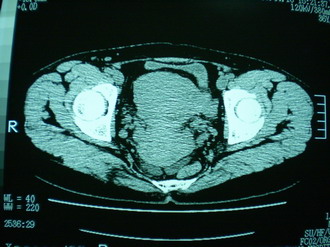

子宫增大,内可见类三角形低密度区,子宫后方可见类圆形团块状影,内部密度不均匀,可见靶样结构,结合病史考虑1子宫后方宫外孕(宫内假孕囊形成)2子宫肌瘤合并妊娠

子宫明显前倾,增大,宫颈增大呈分叶状。子宫直肠窝见不规则形水样低密度。(膀胱胀尿不理想)

考虑:1、宫颈部占位;

2、子宫直肠窝少量积液(盆腔炎所致)。

考虑:1、宫颈部占位(宫颈癌?);

2、子宫直肠窝少量积液。

1、前曲子宫,2、宫颈部占位?3、盆腔及右输卵管积液?宫内积血?4、左侧卵巢囊肿。